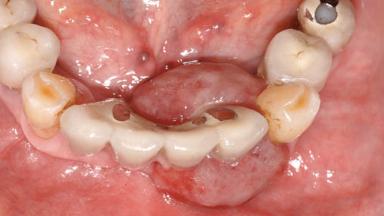

Peripheral Giant-cell Granuloma Associated with Peri-implant Tissues

Giant-cell granulomas (GCG) of the jaws are benign reactive lesions of unknown etiology, unrelated to giant-cell tumors (osteoclastomas), which are defined as benign but locally destructive and aggressive neoplasms (Jundt and coworkers 2005). Depending on their localization at the initial diagnosis, GCG are dived into central (CGCG) and peripheral (PGCG) types. CGCGs occur within the jawbones and appear as unilocular or multilocular radiolucent lesions. The incidence in the general population is very low. They are more commonly found in the mandible, mainly in children and young adults—patients are generally younger than 30 years—and have a greater incidence in females (Heithersay and coworkers 2002). The clinical behavior of CGCGs varies from slowly growing asymptomatic swellings to aggressive lesions that may result in pain, cortical perforation of the affected jaw site, and root resorption (de Lange and coworkers 2007).

Case Type Extended Space

Jaw Mandible

Area Anterior|Posterior

# of Teeth 10

# of Implants 5